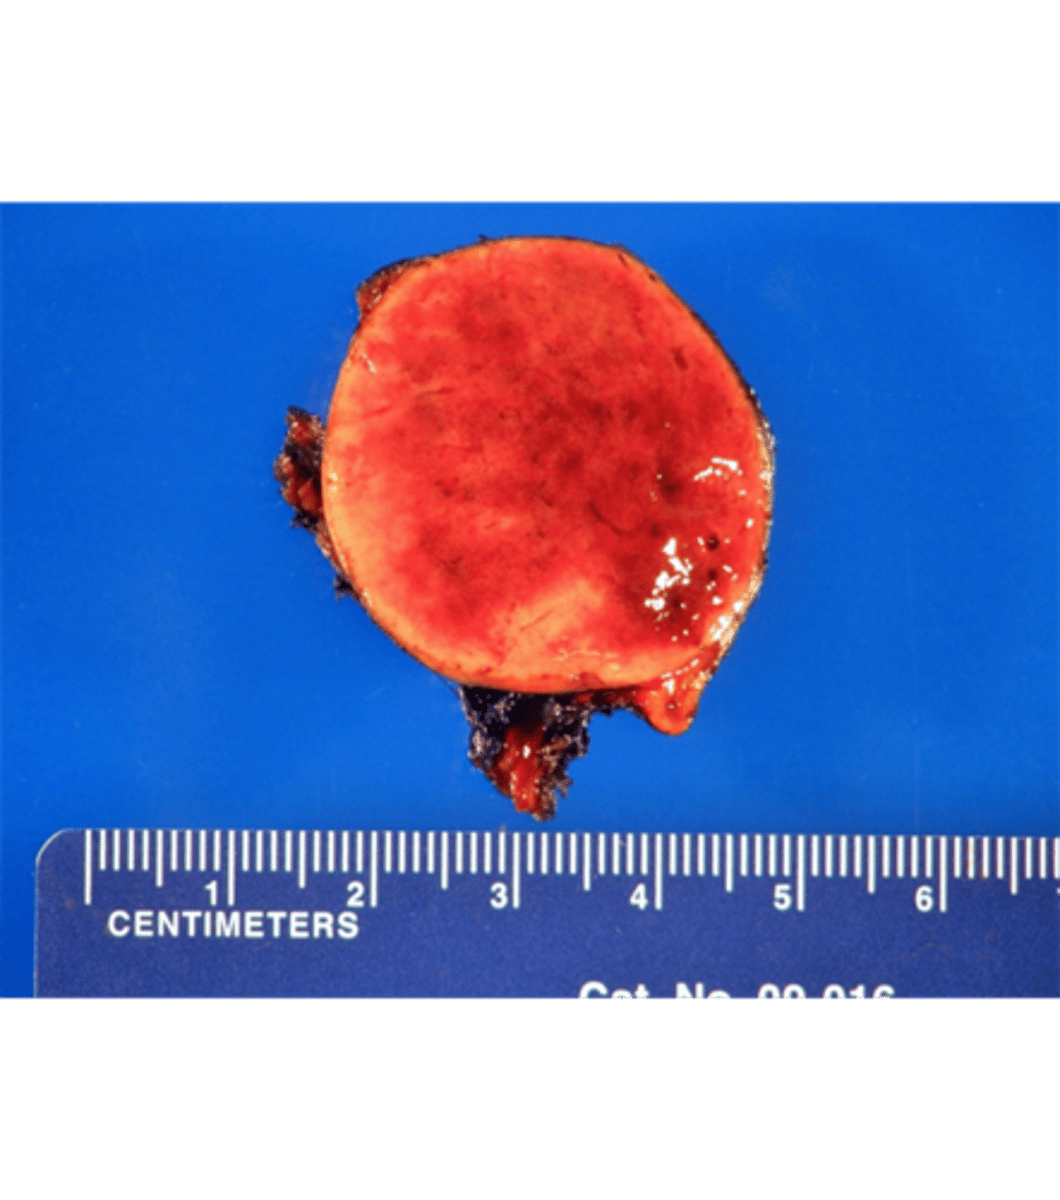

parathyroid adenoma

pathology